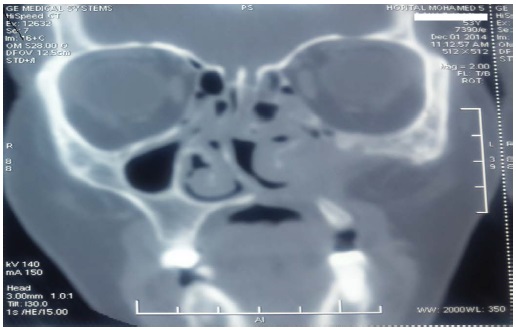

Naso literature review picture This image demonstrates naso literature review.